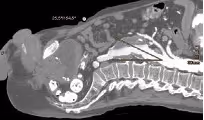

An infrarenal aneurysm,i.e. where there are at least 15mm of non-aneurysmal aorta between the renal arteries and the aneurysm, can usually be treated endovascularly using a standard off-the-shelf stent graft system. However, some additional anatomical conditions must be met for a successful EVAR. These include but are not limited to a cylindrical (as opposed to conical) neck; a neck diameter between 16 and32 (better 28) mm; limited amount of thrombus and calcification in the neck; angulations of the peri- and infrarenal segment within specific limits; a diameter of the aortic bifurcation of at least 16-18mm; iliac arteries that allow the introduction of the delivery systems, are not too kinked and provide adequate sealing zones for the stent grafts.